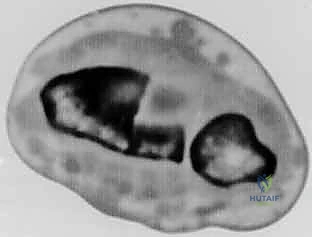

- الأشعة المقطعية (CT Scan) مع إعادة البناء ثلاثي الأبعاد (3D Reconstruction): هذه الخطوة حاسمة. تتيح للدكتور هطيف رؤية العظم من جميع الزوايا، وتحديد مكان القص بدقة متناهية.